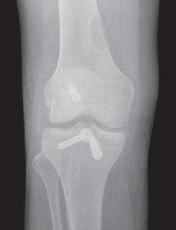

29. This process is then repeated for the PM graft (

TECH FIG 8

).

1. It is helpful to keep tension on the AL graft suture ends when passing the PM graft to ensure that the AL graft does not get pulled into the joint.

30. Graft fixation is performed first on the femoral side.

1. The AL bundle is secured as previously described.

2. This process is repeated for the PM bundle, ensuring that adequate separation exists between the two screws and washers to prevent overlap.

31. An anterior tibial force is applied to reduce the tibia before and during final tibial fixation.

1. Two 4.5-mm cortical screws and washers are placed from anteromedial to posterolateral within the proximal tibia, just distal to the respective tunnels.

2. As with the single-bundle technique, before the screw advances to the second cortex, the suture limbs from the tibial side of the graft are tied with tension over the post, and then the screw is tightened.

3. The AL graft is secured first at 90 degrees flexion, and the PM bundle then is secured at 15 degrees of flexion.

4. The arthroscope is inserted to confirm adequate position, tension, and fixation of the grafts.

--- TECH FIG 8 • The double-bundle reconstruction with the grafts in place. ### TECHNIQUES